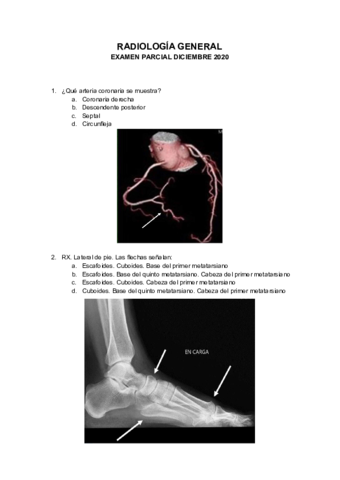

Exámenes - EXAMEN-PARCIAL-DICIEMBRE-2020.pdf